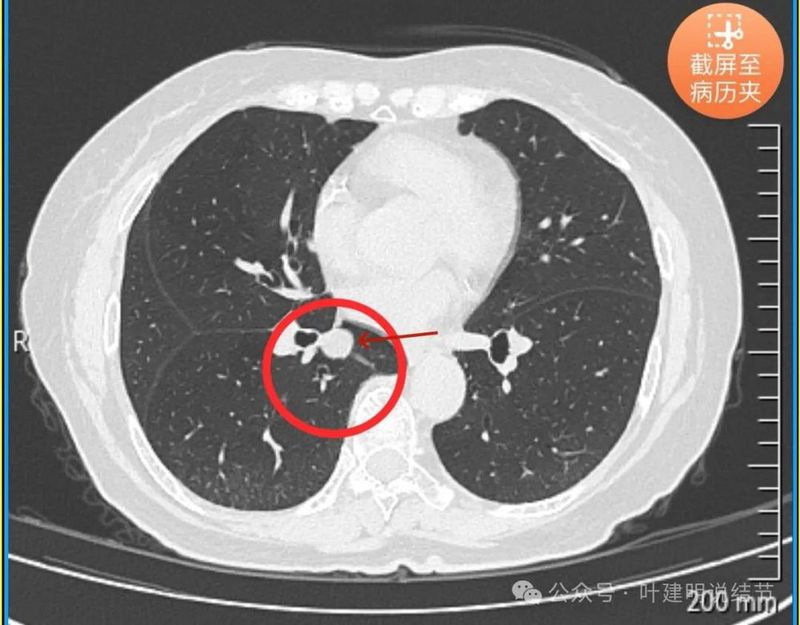

天蓝色箭头示病灶与支气管之间有缝隙,但贴的较近;黄色箭头示支气管管腔;红色箭头示病灶,边缘光滑。

支气管受压,但无明显破坏;与支气管之间紧贴位有的位置仍有缝隙;病灶边缘光滑。

病灶密度较为均匀,对支气管是压迫后移位。表面光滑。

似乎有血管穿过。

边缘光滑,没有毛刺,膨胀性生长。

表面光滑,内部密度较均匀,边界清楚,膨胀性长。